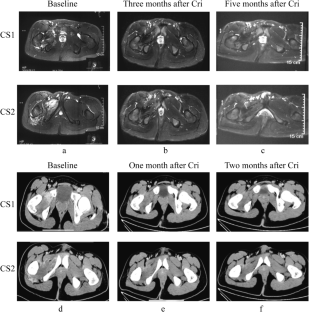

Fig. 1

Fig. 2